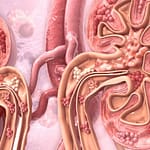

Lee sobre proteinuria en gammapatías monoclonales, Esterasa leucocitaria, carcinoma neuroendocrino de esófago, entre otros